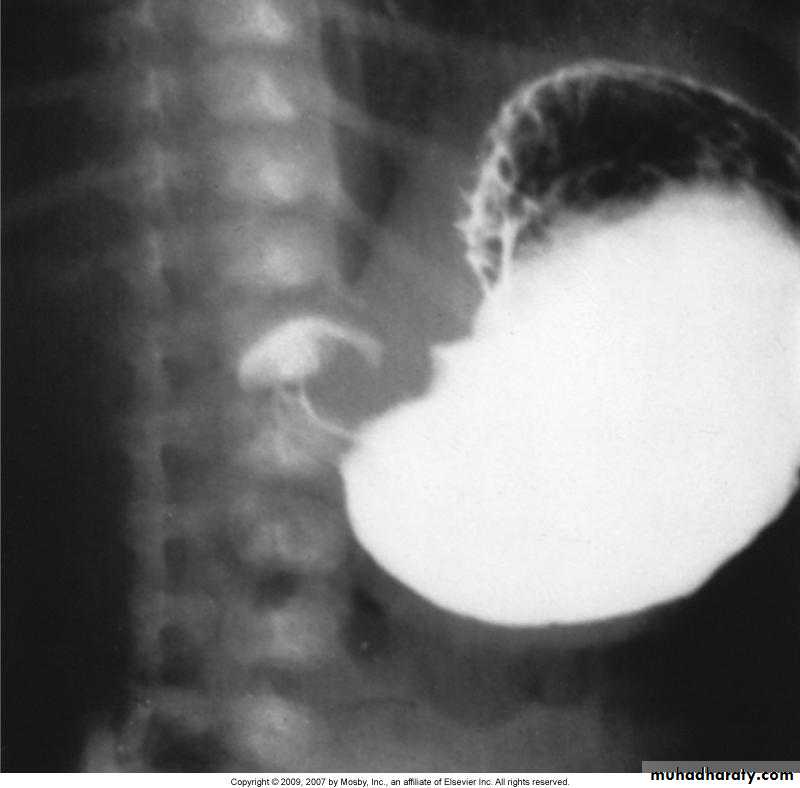

A barium enema shows annular carcinomas as an irregular stricture with shouldered edges (apple-core appearance), usually < 6 cm in length. The polypoid or fungating carcinoma causes an irregular filling defect projecting into the lumen of the bowel.

May arise anywhere in colon but commonest in rectosigmoid and cecum.

In rectosigmoid, it is often annular obstructing stricture whereas cecal carcinoma can become large without obstruction.